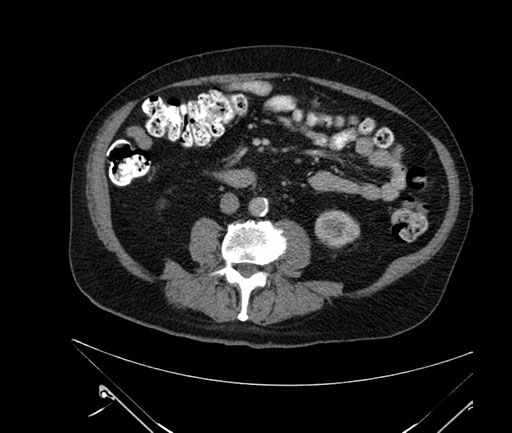

Coronal - stented